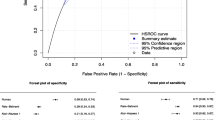

The accuracy of mpMRI in the diagnosis of prostate cancer before the release of the PI-RADS guidelines was first described in a meta-analysis by De Rooij et al. They evaluated seven studies and showed a pooled sensitivity and specificity of 0.78 (95% confidence interval [CI] 0.65–0.87) and 0.88 (95% CI 0.8–0.94), respectively. The negative predictive value ranged from 0.65 to 0.94. The reference standard in these studies was transrectal or transperineal prostate biopsy or radical prostatectomy specimen [23]. Following the introduction of the PI-RADS v1 and v2 guidelines, a meta-analysis showed an increased sensitivity of 0.89 (95% CI 0.86–0.92) and decreased specificity of 0.73 (95% CI 0.60–0.83) for prostate cancer detection [24]. A head-to-head comparison of PI-RADS v1 and v2 in six studies showed a higher pooled sensitivity for PI-RADS v2 of 0.95 (95% CI 0.85–0.98) compared to 0.88 (95% CI 0.8–0.93) for PI-RADS v1 [24].